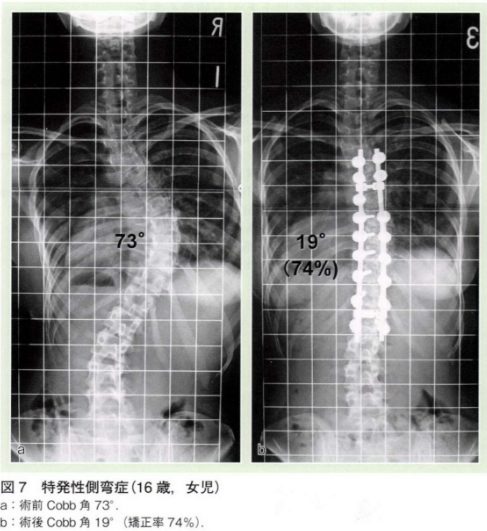

小学校や中学校の学校検診で姿勢の異常でひっかかり、当院を受診する方は比較的多いです。その中でも多い病気として胸椎や腰椎が曲がってしまう側弯症という病気があります。8割は原因が分かっていない特発性側弯症であり、女児に多いと言われています。進行すると装具治療や手術治療が必要となる方もいらっしゃいます。予防する方法はわかっていませんので、早期発見することが重要となってきます。

診察で上記の図のような肋骨隆起やウエストラインの非対称などを確認します。またレントゲンを撮像し、Cobb角を測定することで、胸椎や腰椎のカーブがあるかを確認します。

治療方法は側弯のカーブの角度によって分かれます。カーブの角度が24度以下は要経過観察の対象となり、成長段階の場合は4カ月に1度レントゲンを撮り、側弯の進行がないか確認します。角度が25度以上の場合は装具治療の適応となります。装具治療には脇下からのアンダーアームブレースが主に使用されています。

角度が45度以上で、骨が成熟している場合は手術を考えます。手術は金属製の内固定材による矯正固定術と骨移植術が中心となります。医学の進歩により矯正率は60-70%と目覚ましく上昇しております。手術の目的は、見た目の問題もありますが、最も重要なのは側弯の進行予防です。45度以上の側弯は、成長期を過ぎてからも少しずつでありますが進行することが多く、長期的には重症側弯に進行することが知られています。中高年以降で重症側弯に進行した場合、心肺機能の悪化や神経症状を生じることもあります。10歳代の段階で側弯を矯正し進行を防止することにより、将来的な健康に対する不安を払拭することが重要です。